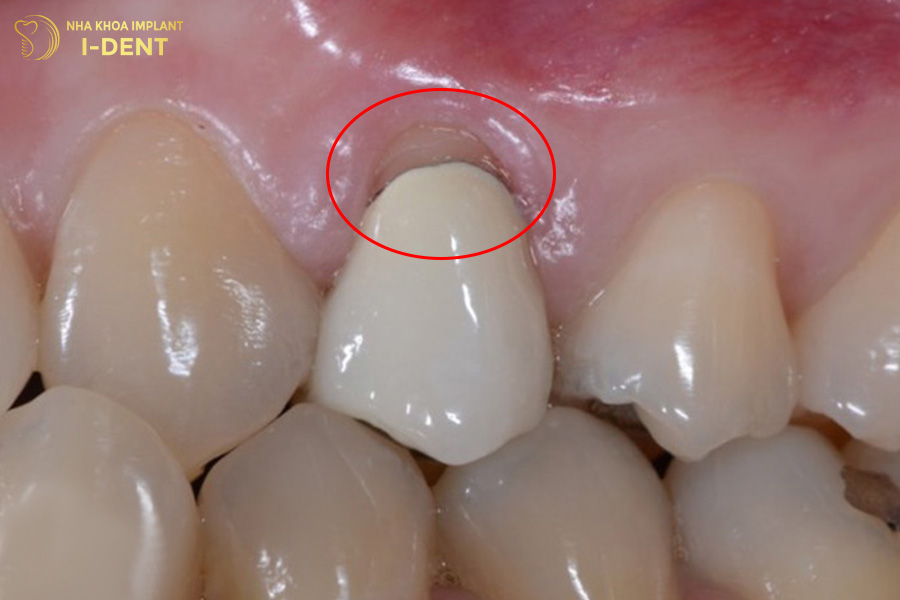

1.2. Tụt nướu làm lộ cùi răng bên trong

Bọc răng sứ sai kỹ thuật sẽ tạo ra khoảng hở giữa mão sứ và nướu. Khe hở này tạo điều kiện thuận lợi để vi khuẩn xâm nhập, gây viêm nướu và dẫn đến tình trạng tụt nướu. Khi nướu bị tụt, phần cùi răng hoặc chân răng sứ bên trong bị lộ ra ngoài.

Dấu hiệu răng sứ bị hở kiểu này thường rõ ràng nhất ở những vị trí dễ quan sát như răng cửa hoặc răng nanh.

Tình trạng răng sứ bị hở làm lộ phần cùi răng bên trong.